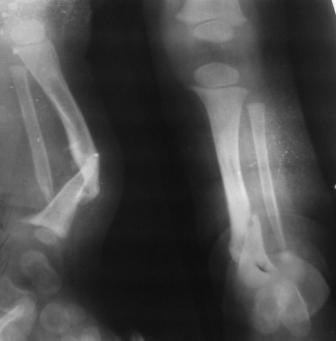

Глубокоуважаемые коллеги женщины! Поздравляем с праздником ВЕСНЫ, Международным женским днем - 8- МАРТА, здоровья , благополучия и успехов во всем! Ребенок 1г, мальчик, от первой беременности, родился без патологии весом 4кг, родители травму исключают, постепенно заметили деформацию н/з голени, которая начала увеличиваться . Брак родственный. Об-но; имеется угловая деформация открытым углом кзади на уровне н/з голени, ригидная , коррекции поддается мало. Функция коленного и г/с суставов не нарушены. Уважаемые детские ортопеды! Почему такое упорное молчание ортопедов! Я искреннее прошу прошения , если можно , мы нуждаемся в Ваших советах! План лечения; этапное, дистракционный аппарат, коррекция деформации, остеотомия в/з б/б кости, удлиняющая дистракция в обл остеотомии с одновременной компрессией в обл псевдоартроза и наблюдение , дальше по обстоятельству Вопросы; . 1. В каком возрасте можно начинать лечение, какие еще варианты лечения? 2. На Р-грамме как будто имеется недоразвитие дистального эпиметафиза м/берцовой кости, тогда что можно делать? С уважением Абдурашид.

Врождённый Псевдоартроз Голени (ВПГ) – редкое заболевание б частота 1: 190000 живых новорожденных.

До 1930 года ампутация была регулярной процедурой. Но в последние 80 лет произошла смена представления к лечению ВПГ. Около 70% пациентов псевдоартроз большеберцовой кости (б/б) сопровождается таковым малоберцовой (м/б).